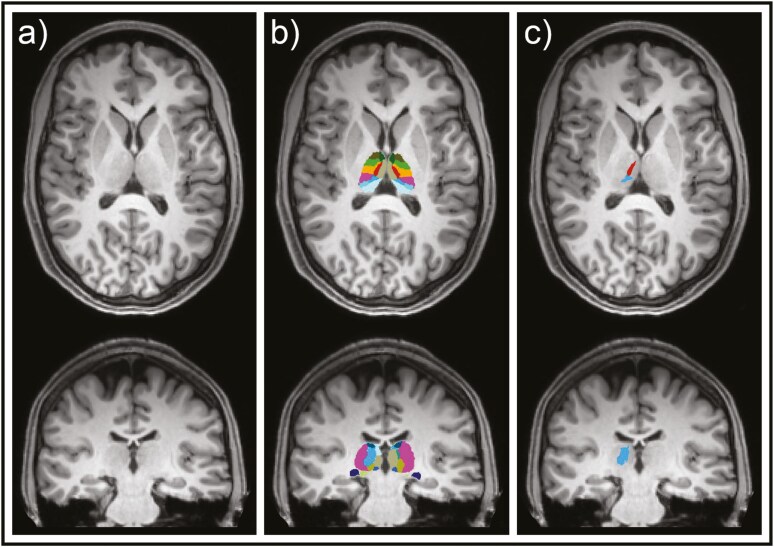

Methods: Twenty-six subjects (14 female, mean age ± SD = 24.3 ± 3 years) underwent two magnetic resonance imaging scans on a 3T system immediately after receiving a subanesthetic dose of 56 mg esketamine (2x Spravato 28mg nasal sprays) or placebo in a cross-over study design. FreeSurfer was used for morphological analysis of the thalamus and its distinct nuclei based on derived T1-weighted MPRAGE images. Repeated measure analyses of covariance across the whole group, regardless of measurement order, and the subgroup, receiving placebo in the first scan, were performed for the thalamus and all its nuclei, for each hemisphere, separately. Post hoc tests on thalamic nuclei were done in an exploratory manner.

Results: We found a significant volume increase in the right thalamus (pcorr. = .048), the pulvinar anterior nucleus (p = .048), and the right mediodorsal lateral parvocellular (p = .034) after esketamine in the subsample receiving placebo application in the first scan.

Conclusion: Our results suggest rapid structural adaptations in right thalamic structures which serve as relay stations for the visual cortex. This emphasizes the thalamus' role in visual perception after esketamine and its importance as a target to model schizophrenic symptoms.